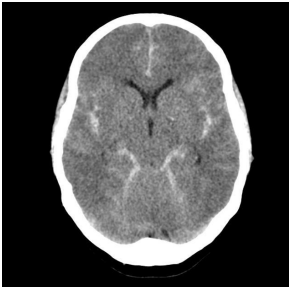

As urgências neurológicas tem importante prevalência em nosso meio. Seu diagnóstico precoce pelo médico assistente do paciente, através da tomografia, é essencial para o bom prognóstico e evolução do paciente.

https://radiopaedia.org/articles/subarachnoid-haemorrhage

Uma paciente de 23 anos trazida inconsciente, sem história de trauma, dá entrada na sala de emergência e realiza essa tomografia. Qual seria uma possível causa para a principal alteração tomográfica?